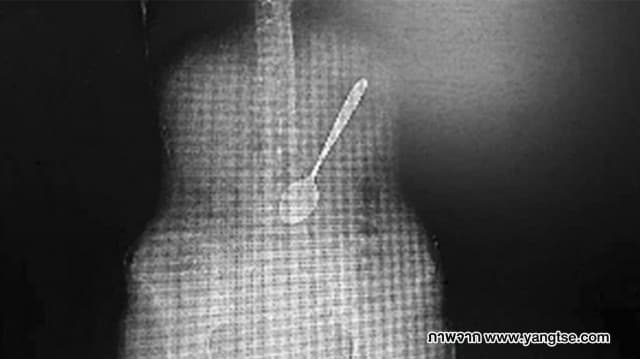

หญิงจีนพลาดกลืนช้อน 15 เซน ลงท้อง ระหว่างซดก๋วยเตี๋ยว